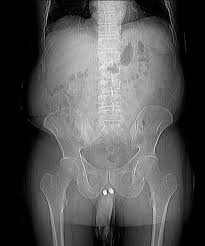

Penile Implant | The main reason as to why this happens is that following the penile implant, the glans or … Blood clots in penile tissue; Make sure you discuss realistic expectations for. Most patients experience a slight decrease in penile size following the penile implant surgery.the reduction is small and is on the order of ¼ of an inch.